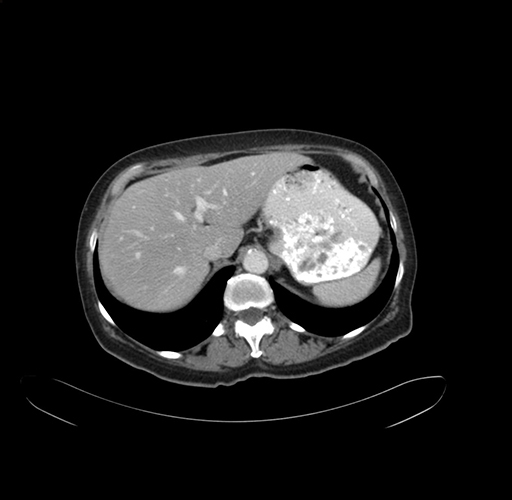

Axial Venous